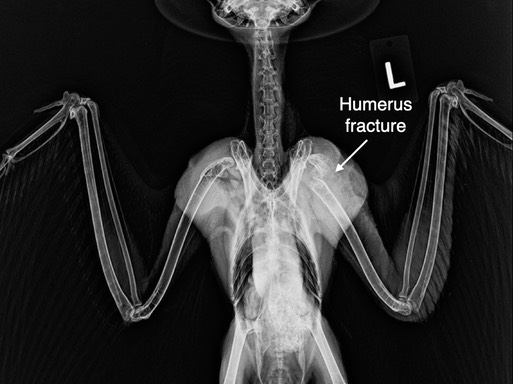

There were just seven admissions this past week, all but one a raptor. Of four Great Horned Owls, three had humerus fractures, the fourth was tangled in a fence, none could be saved. A Sharp-shinned Hawk was shot and a Red-tailed Hawk was likely struck by a vehicle. Neither could be saved. Living in a world filled with humans is no easy task for wildlife.

Great Horned Owl 21-759